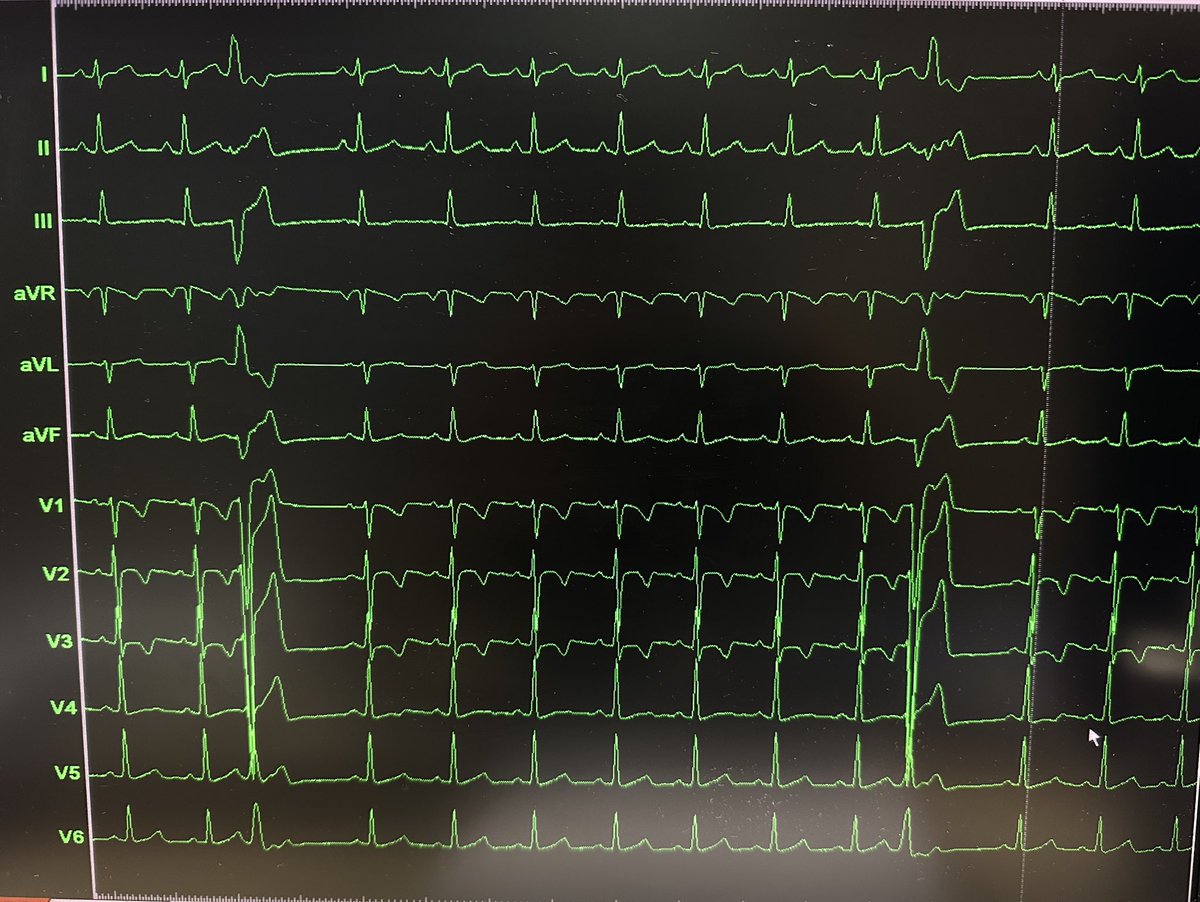

Surprise spontaneous ORT using a concealed left lateral pathway on a younger patient (early 40s) scheduled for PFA AF ablation (history of persistent AF). Should we still proceed with the PVI? #EPeeps